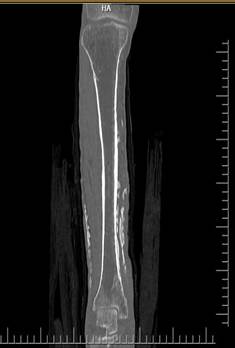

Inicialmente consultó en el hospital local, donde iniciaron manejo antibiótico con clindamicina y ampicilina-sulbactam, con posterior exposición ósea y miasis, por lo que remitieron a una institución de mediana complejidad, donde administraron una dosis única de ivermectina, con curación completa de la miasis. Sin embargo, hubo persistencia de la exposición ósea por lo que se decidió remitir a una institución de alta complejidad para manejo multidisciplinario, con el diagnóstico de sospecha de osteomielitis de tibia. Al ingreso a la institución se realizó una radiografía AP y lateral de la pierna derecha donde se apreciaba una zona calcificada en la región medial de la extremidad, la cual se puede observar en las Figuras 2 y 3.

Figura 2 Radiografía AP de pierna derecha.

Figura 4 Corte coronal en tomografía axial computarizada simple de pierna derecha.